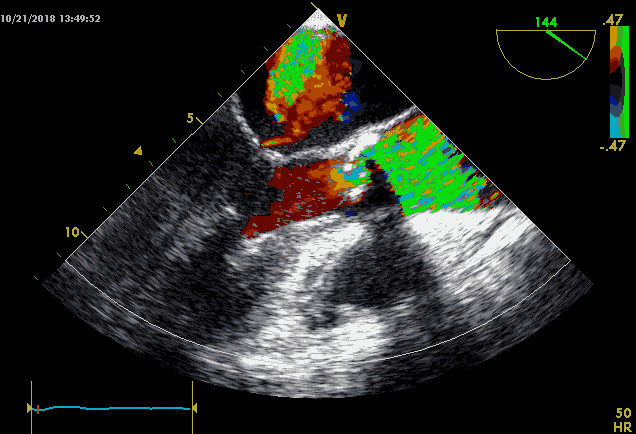

>>心超:

重度主动脉瓣狭窄伴反流,室间隔及左室壁增厚,左房扩大伴二尖瓣反流,右房扩大伴三尖瓣反流,主动脉增宽,左室舒张功能减退。

术前心超提示type1型二叶瓣,闭合受限,返流明显